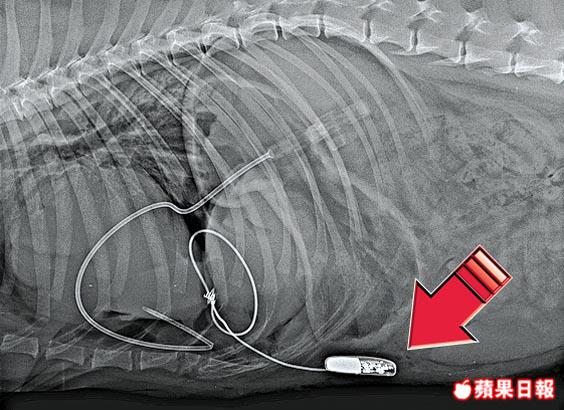

Ken稱,Oscar接受手術前病情危急,心跳只有每分鐘30下,遠低於正常的80下,每天最少10次突然暈倒。他指出,美國多年前已開始為狗隻植入心臟起搏器治療同類病症,本港獸醫過去無相關手術經驗,但考慮到Oscar病情危急,狗主同意由他操刀,在診所進行相關手術。

手術前晚進行,歷時90分鐘,需要兩名醫生及3名護士協助,任職獸醫診所護士的狗主Anna亦有參與。Ken指狗隻使用的起搏器與人類相同,可使用4至6年,期滿後需要再動手術更換起搏器,但拉布拉多犬壽命最多14歲,相信足夠讓Oscar度過餘生。